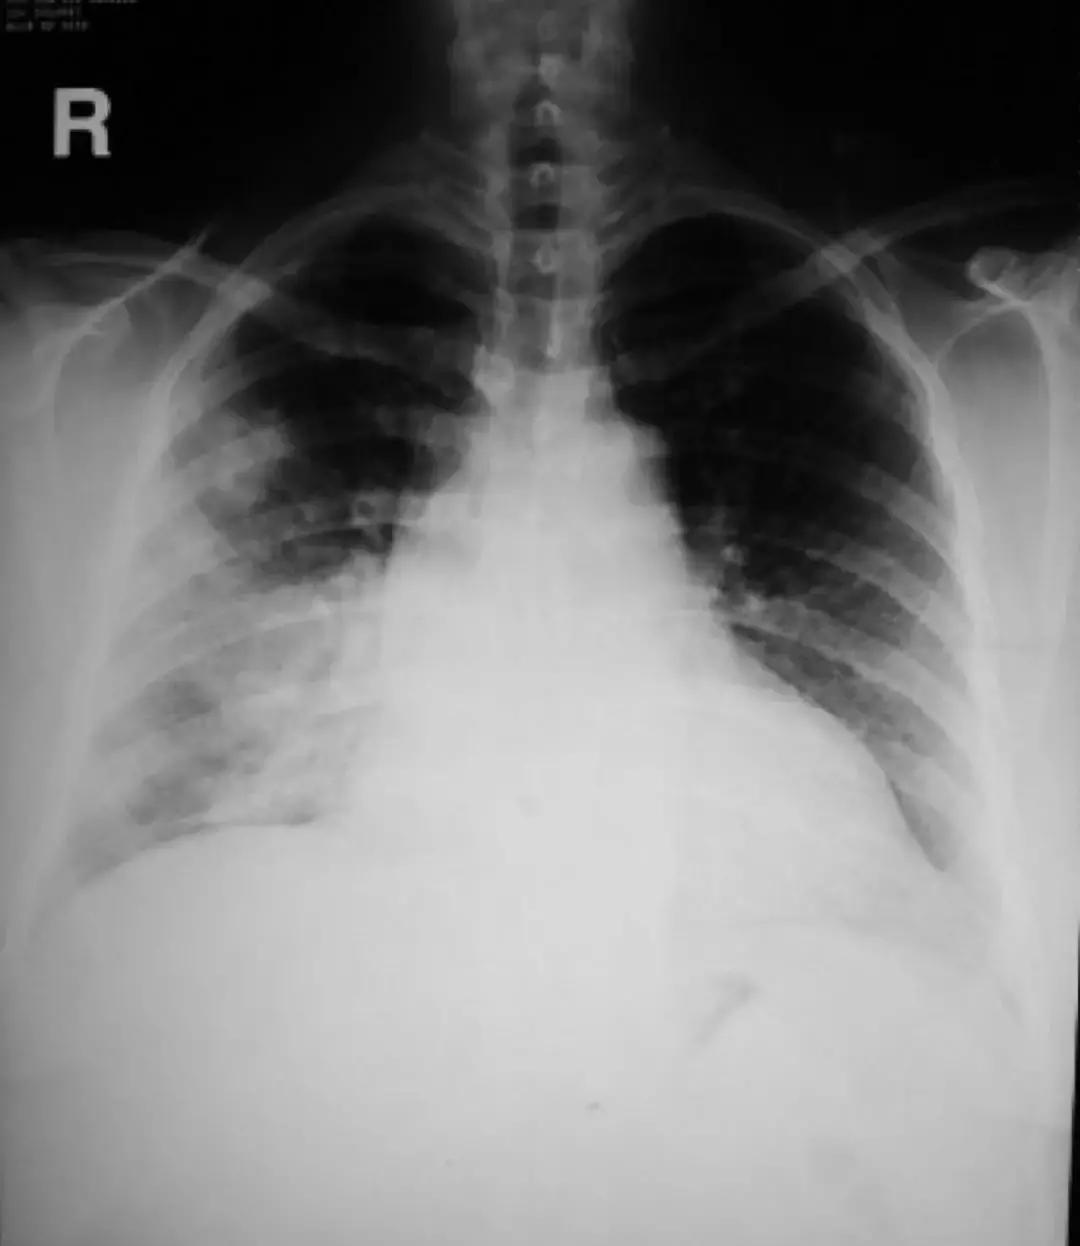

对于肺部感染的诊治来说,细菌、病人、抗菌药物、医生……到底谁是赢家?一切皆有可能!所谓「谍影重重」,就是胸部CT上的各种影像,一提到胸部CT,大家最容易想到的就是下图中在临床上最常见的影像学图像:

这种影像绝大部分是肺炎,在基层医院肺炎最常见的治疗方法是抗菌药物、皮质激素、维生素。

先来看看这张胸部CT :

这是一个20岁的女性,高热、咳嗽伴呼吸困难1周,血气分析:Ⅰ型呼吸衰竭,血常规:正常。可以看到影像学是在进展的。

那么是不是肺部感染(CAP)?很难诊断,于是做了肺穿刺。两次肺穿刺活检为慢性炎症改变,应用皮质激素治疗,症状缓解,复查病灶基本吸收。最后诊断为肺血管炎病变。